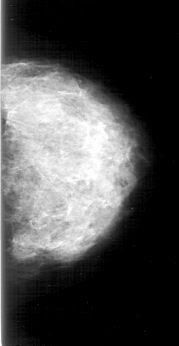

D_4192_1.RIGHT_CC

RIGHT_CC LINES 5986 PIXELS_PER_LINE 3076 BITS_PER_PIXEL 12 RESOLUTION 43.5 OVERLAY